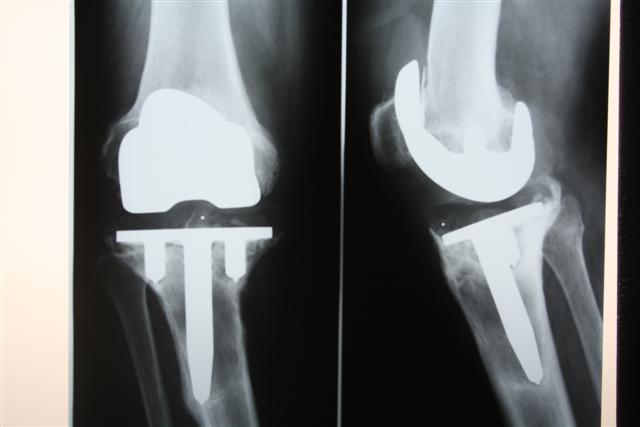

Первичное эндопротезирование коленного сустава

На сегодняшний день общепризнано, что эндопротезирование тазобедренного и коленного суставов является единственным эффективным методом лечения при разрушении суставного хряща и позволяет избавит пациента от боли и вернуть его к активной жизни. В мире ежегодно выполняется более полутора миллионов таких операций. Современные эндопротезы служат десятки лет и позволяют жить полноценной жизнью даже молодым и активным пациентам, а в случае, если эндопротез всё же износился, его можно заменить на более сложный и продолжать пользоваться всеми благами жизни.